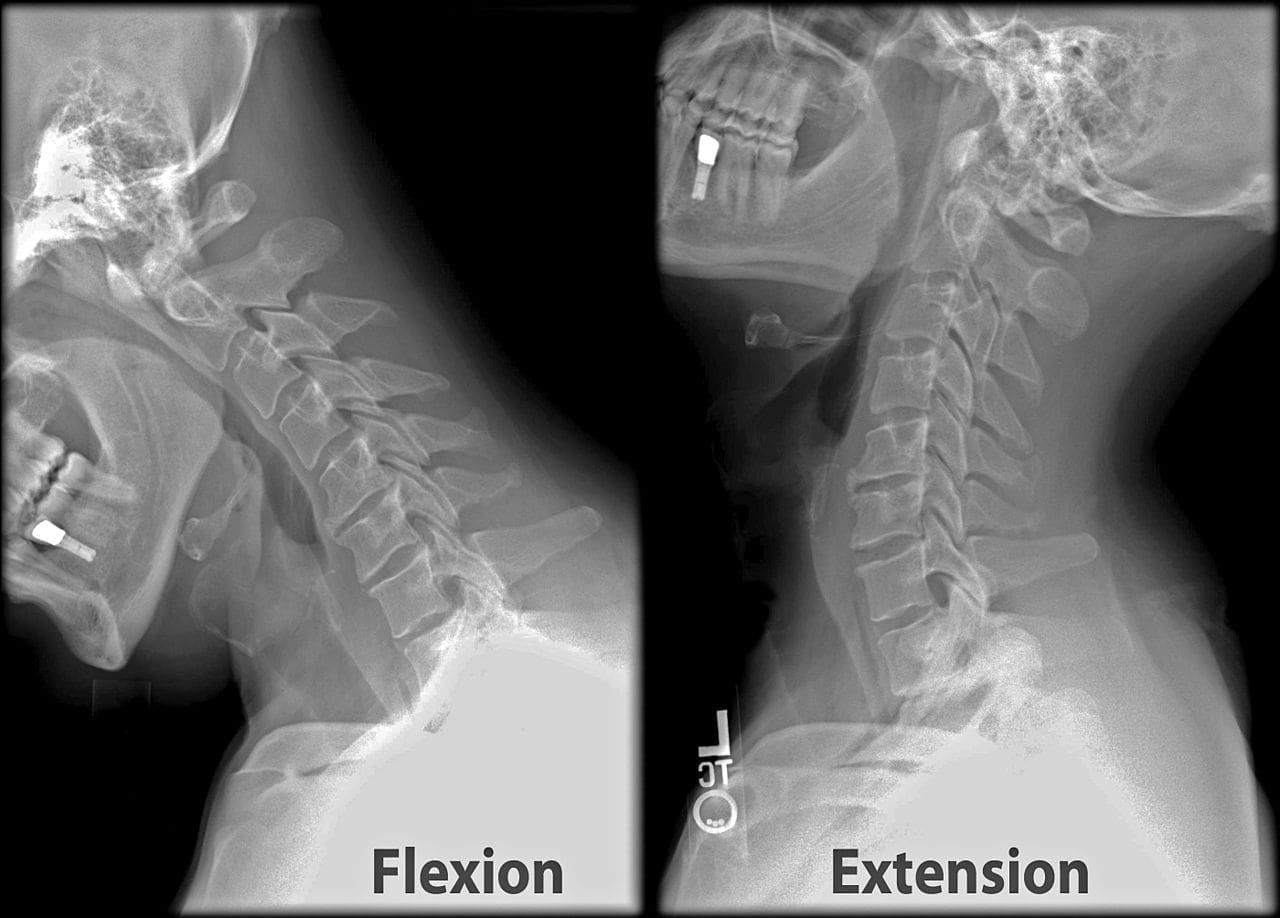

After a car crash, compression fractures are common in the thoracic and cervical spine (middle and lower back). While the entire body is held in place with a seatbelt, the body may be thrown forward during impact. This can pull on the vertebrae. As the vertebrae may rarely move, in some cases, spinal fractures may result in spinal cord injuries. Those with spinal cord injuries may experience tingling, numbness, weakness, or bowel and bladder control loss. However, the main symptom of a spinal fracture is mild to severe back pain that interferes with movement. When a fracture is suspected, it is essential not to move the injured person; harm could be caused by motion.

Spinal Fractures

Spinal Fractures